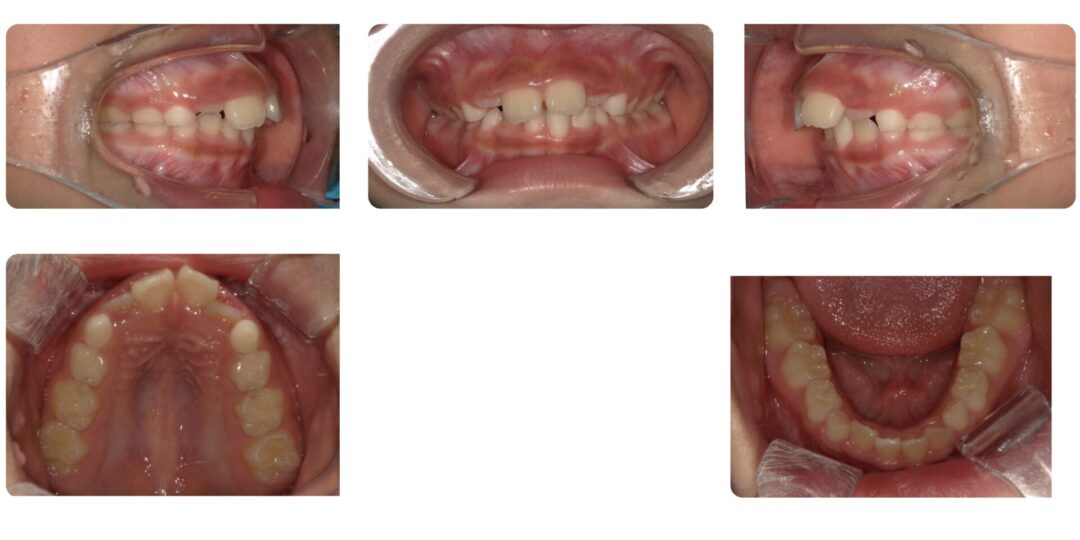

過蓋咬合を伴う骨格性上顎前突|初診時7歳

矯正治療前